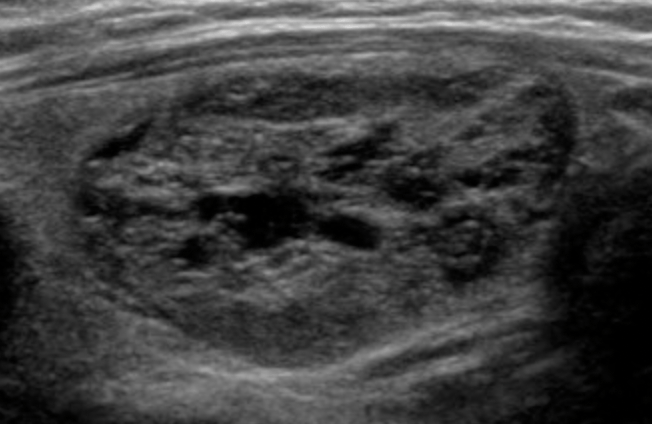

- Composition:

- Nodules that are cystic or almost completely cystic merit no points because they are almost universally benign

- A spongiform architecture is highly correlated with benign cytology:

- Regardless of its relative echogenicity or other features

- However, a spongiform nodule must be composed predominantly (greater than 50%) of small cystic spaces

- Nodules should not be characterized as spongiform solely on the basis of the presence of a few, scattered cystic components in an otherwise solid nodule

- “Mixed cystic and solid” combines two features from the lexicon, predominately solid and predominately cystic

- The appearance of the solid component is more important than the overall size of the nodule or the proportion of solid versus cystic components:

- In determining whether biopsy is warranted

- Solid material that is eccentric and has an acute angle with the nodule’s wall is suspicious, as is:

- Solid material with moderately or highly suspicious characteristics, such as:

- Decreased echogenicity

- Lobulation

- Punctate echogenic foci